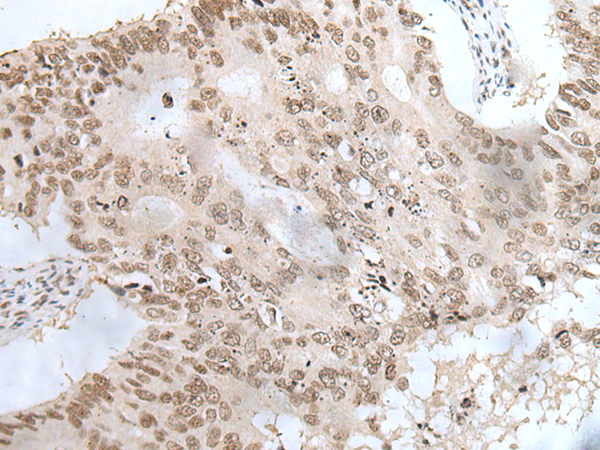

IHC positive control:

Human colorectal cancer and human ovarian cancer